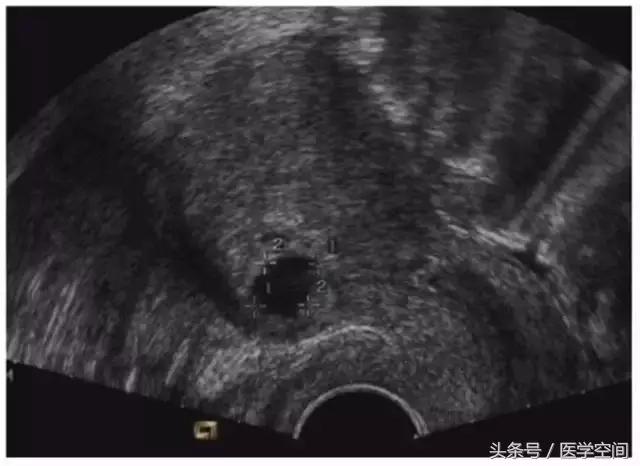

1.1典型CSP的超声表现

CSP是指妊娠囊着床在前次剖宫产子宫切口的瘢痕处,典型CSP的超声表现主要有:妊娠囊位于前次剖宫产子宫切口处,宫腔内及宫颈管内没有孕囊,邻近膀胱处的子宫肌层变薄(见图1)。呈典型表现的瘢痕妊娠CSP超声诊断很容易。

图1典型CSP的超声表现